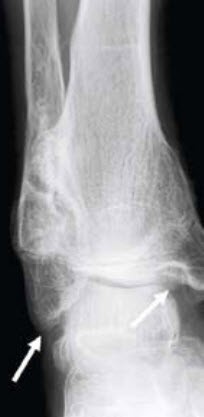

Im Gegensatz zu früheren Vermutungen ist die bösartige Entartung bei der multiplen kartilaginären Exostosenerkrankung sehr gering und liegt laut Literatur bei ca. 0.9 bis 5 Prozent. Im Verdachtsfall wird vor der operativen Behandlung eine MRI-Untersuchung empfohlen. Abb. 7–9 zeigen eine sekundäre Deformierung des oberen Sprunggelenks. Die weissen Pfeile zeigen den sekundären Aussenknöchelhochstand und die sekundäre Diastase von Innenknöchel und Sprungbein. Die Behandlung erfolgte durch Resektion der Exostose und Verlängerung des Wadenbeins unter Beckenkamminterposition und Plattenfixation (schwarzer Pfeil) sowie zeitgleicher supramalleolärer Derotationsosteotomie mit Platte. Das Ausheilungsbild am Ende des Wachstums zeigt ein wiederhergestelltes korrektes Alignement des Sprunggelenks.